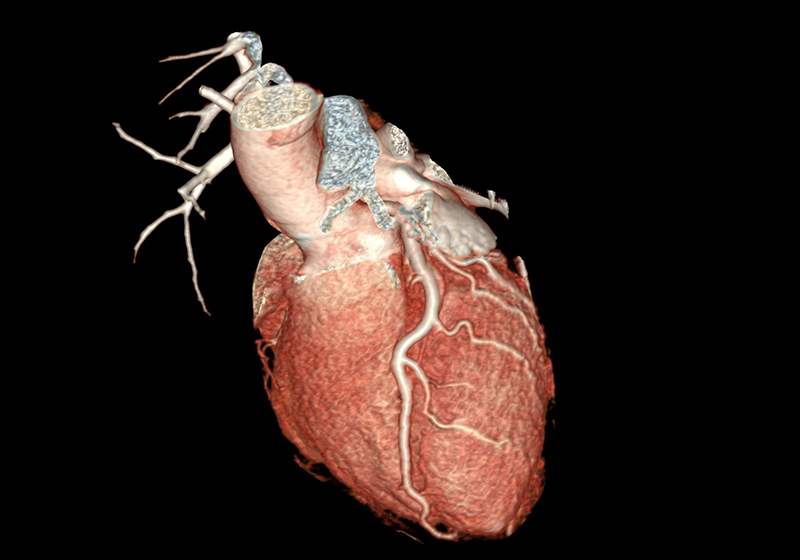

Über eine 3D-Nachverarbeitung werden die Herzkranzgefäße sowie eventuelle Engstellen und Verkalkungen dargestellt und vermessen. Sofern vorhanden, können an dieser Stelle auch Stents oder Bypässe auf deren Durchgängigkeit überprüft werden.